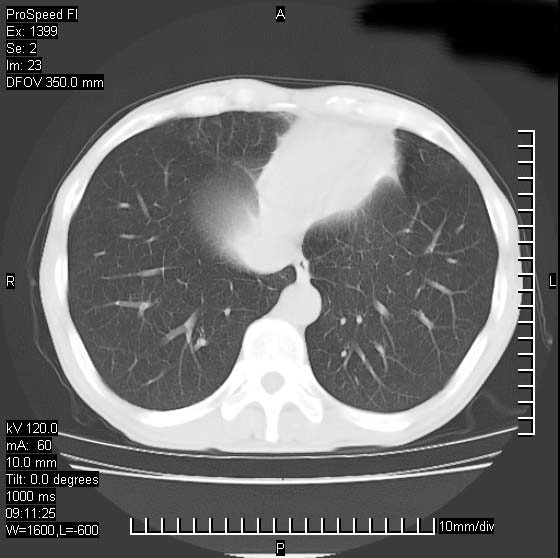

以下是引用卜一在2007-1-19 9:55:00的发言:[br]左肺沿胸膜下巨大肿块影,边缘呈分叶征,纵隔内见肿大淋巴结,右肺内另见一不规则结节影 .考虑:左肺周围性肺癌伴纵隔 右肺内转移.

以下是引用rgsyyf在2007-1-19 11:05:00的发言:[br]左肺上叶见形态不规则巨大软组织肿块影,边缘呈分叶征,纵隔内隆突下见肿大淋巴结,右肺内另见一不规则结节影 .考虑:左肺周围性肺癌伴纵隔即右肺内转移.